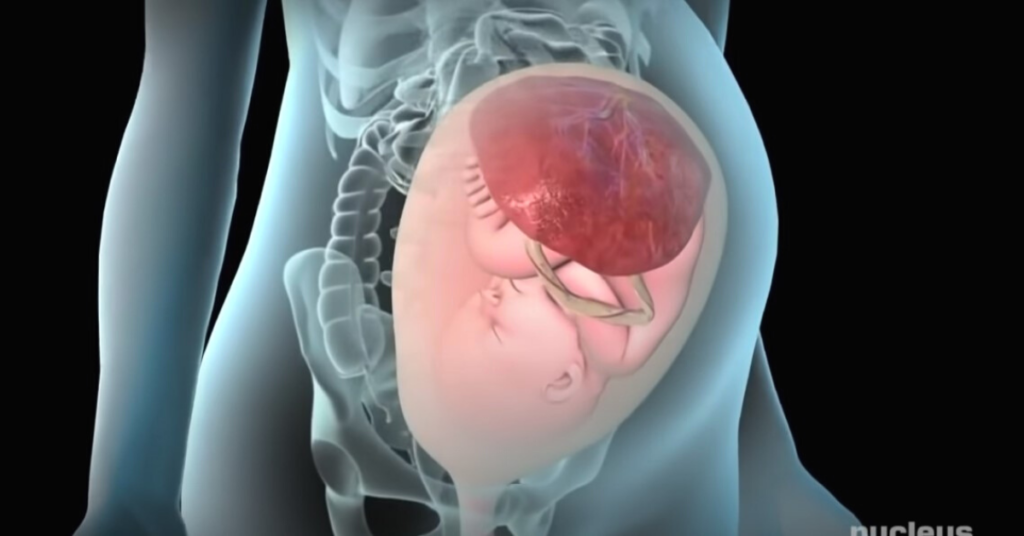

Čim se beba rodi odnosno žena porodi trebalo bi da se ostvari direktan kontakt između majke i novorođenčeta (koža na kožu). Beba se ne kupa, a upravo spajanje kože na kožu štiti novorođenče od raznih infekcija. Ukoliko je porođaj prošao bez problema, prvih pola sata nakon porođaja trebalo bi da prvi put podojite vašu bebu. Vi i vaša beba trebalo bi da budete smeštene u istu sobu, ali bi takođe na vaš poziv zbog umora trebalo da dođe medicinska sestra koja je dužna da se brine o bebi nekoliko sati u toku dana i noći. U okviru programa medicinske sestre su u obavezi da vam pomognu oko dojenja na svaki bebin zahtev. Dužne su da vam pomognu kod učenja pravilne tehnike izmlazanja mleka.

Bebi frendli je idealan za žene koje se porode prirodnim putem sa što manje lekova koji se koriste za izazivanje kontrakcija. Takođe idealan je i za bebe koje nisu imale nikakve komplikacije pri rođenju.

Najveća prednost je rano ostvarivanje veze između majke i novorođenčeta. Kontakt koža na kožu, čim se beba rodi pomaže majkama da se psihički adaptiraju na novu situaciju. Ovaj kontakt pomaže da beba dođe u dodir sa maminom kožom, njenim dodirom i mirisom. Bitan je i prvi podoj. Beba se odmah po rođenju ne odvaja od majke već se povećava instinktivna potreba za sisanjem.

Ja sam se porodila prirodno, vaginalno, bez lekova sa svoje troje dece.. nakon poroda, stavili bi mi bebu na grudi (bilo mi je ponuđeno i da sama prihvatim bebu pri samom porodu). Nakon 30tak minuta beba počne da sisa. Najlepši osećaj na svetu..

Žene su do pre 150 godina prirodno radjale ali se sad nažalost porođaj tretira kao neka vrsta bolesti gde su potrebne anestezije i slično. Ako je zena zdrava a i beba, sto se danas srećom moze tačnije utvrditi nego ranije, ne treba da se plaši jer je njeno telo napravljeno da radja kao sto su i druge žene hiljadama godina..